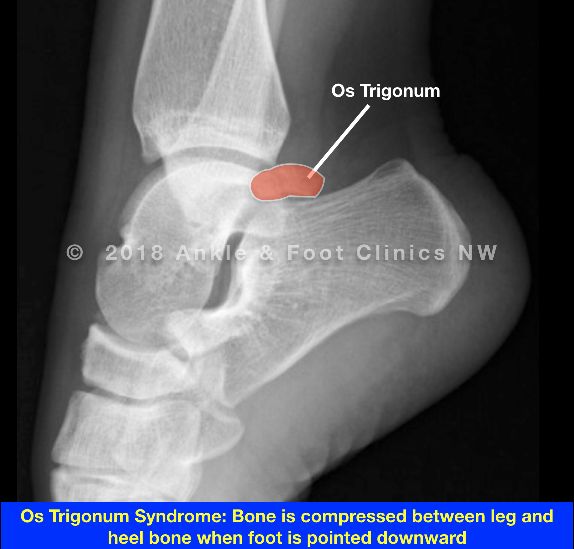

大多数后撞击综合征与距骨后方相关。距骨后外侧的继发骨化中心在8-13岁左右形成,随后在1年内融合。偶尔(约7%),可能与形成的距后三角骨不融合。此外,这个骨化中心可能仍然突出所谓的“Stieda's突(距骨后突)”(图11)。

图11。

(a) 上图显示距骨后突、距后三角骨(OT)和Stieda突的正常后突;(b)从踝关节后视图所示,显示后外侧踝关节的韧带解剖。PITFL,胫腓后下韧带;PTFL,距腓后韧带。

常规射线照相术的初步评估可能表明外观正常,但应特别注意侧位片上是否存在Stieda突或os三角。由于这些也常见于无后撞击综合征症状的患者,不一定引起撞击综合征;但是,在适当的临床背景下,它们可能有助于症状的产生。